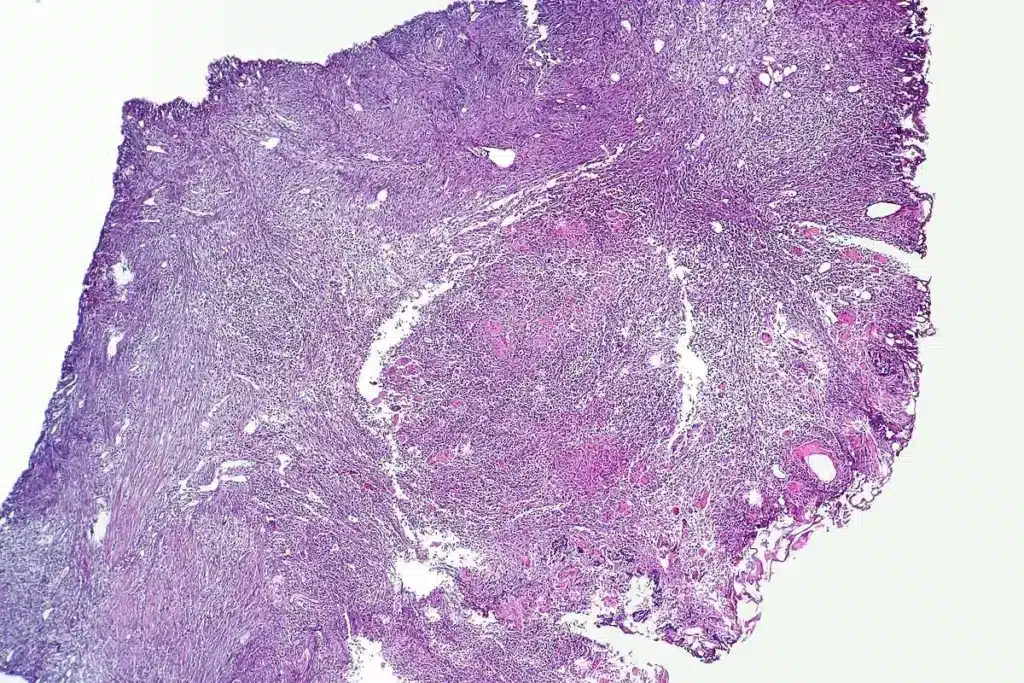

Dermoscopy and Advanced Imaging

Dermoscopy is a way to look at skin without hurting it. It helps doctors see things they can’t see with their eyes. This helps tell if a mole is safe or not.

They might also use digital dermoscopy and confocal microscopy. These tools give detailed pictures of the mole.